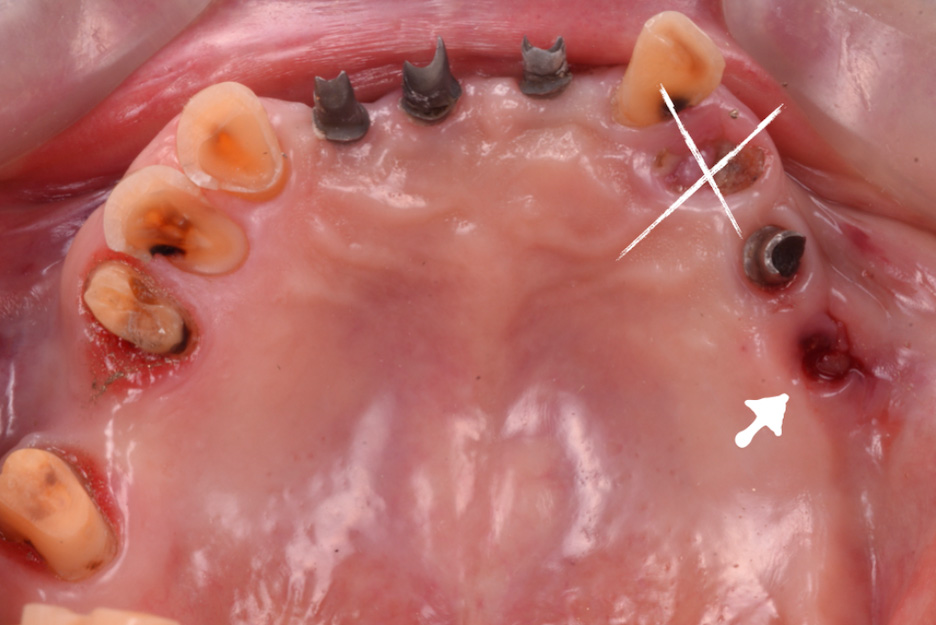

治療前

治療後

| 治療内容 | インプラントと補綴治療 もともと入っていたインプラントを利用しながら全顎的に治療をした。 二度のプロビジョナルレストレーションを経ることにより最良の結果を得ることができた。 |

| 治療に伴うリスク | インプラント周囲炎 補綴物の破損 |